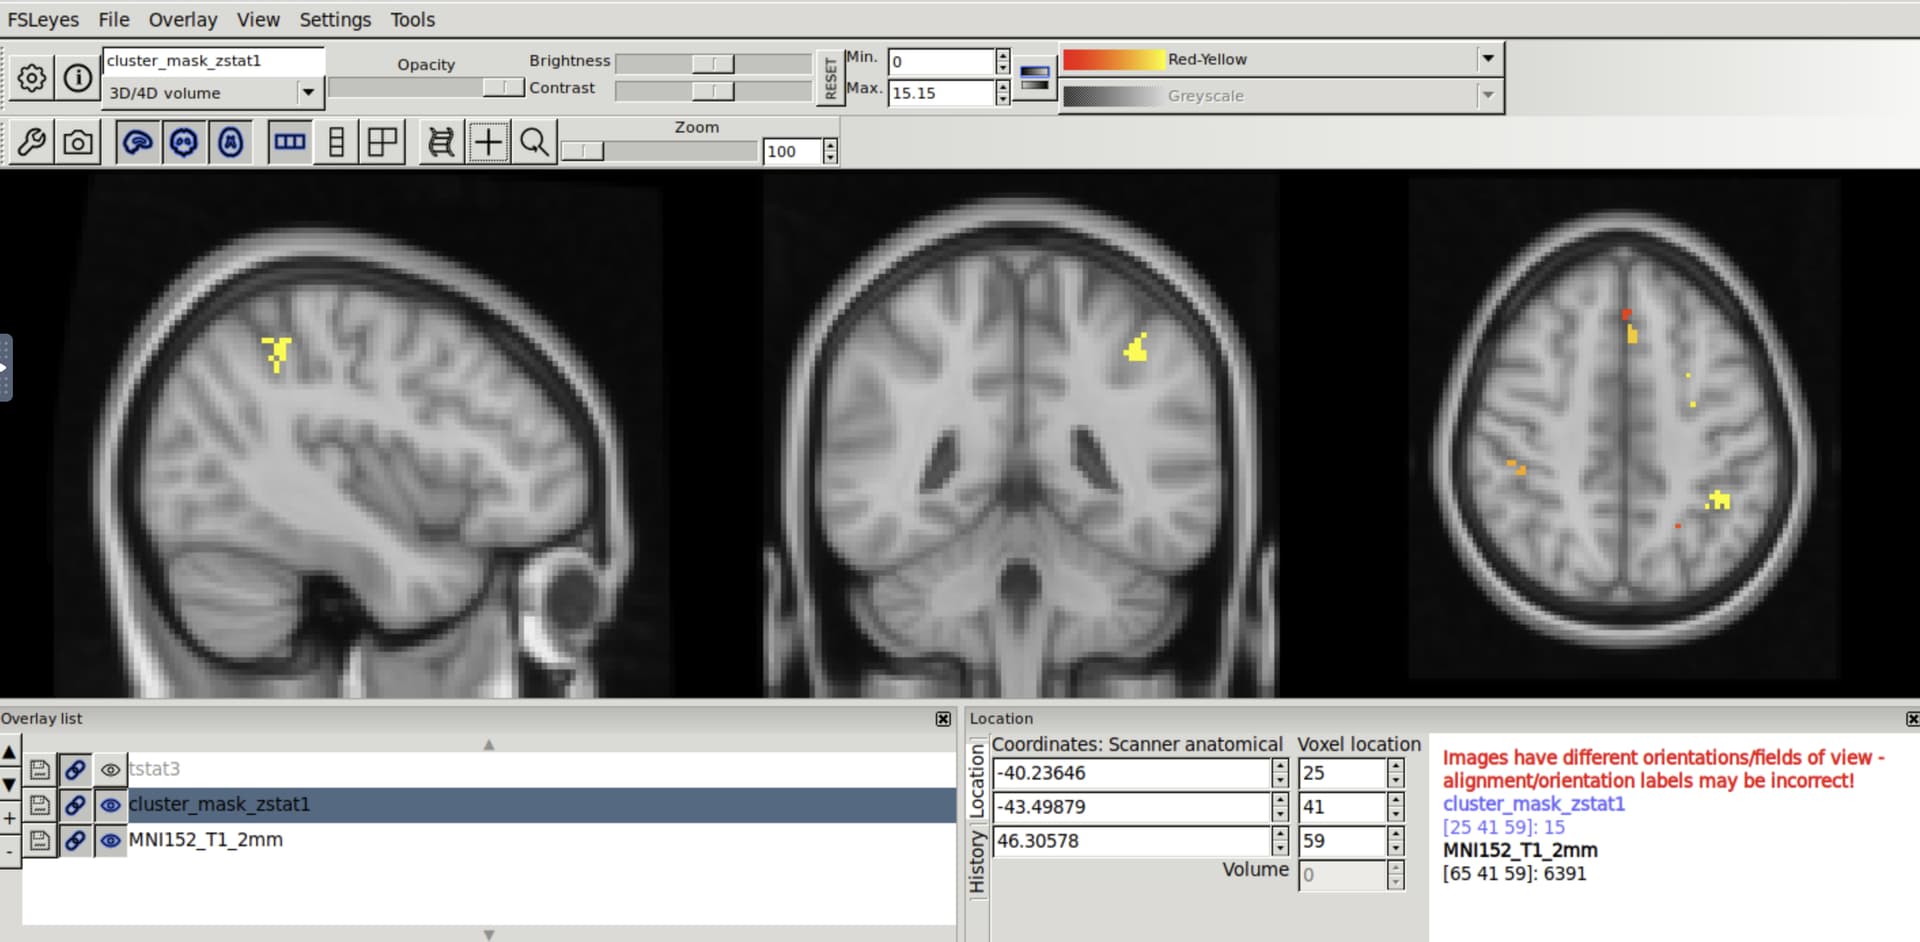

I used fMRIprep to preprocess some functional task data. Then, I ran stats using FSL’s feat (following this Mumford Brain Stats — FEAT registration workaround to deal with registration stuff). When I ran fMRI prep, I used the output space MNI152NLin6Asym, which is believe is the standard space for FSL. However, when I open my contrast results on top of the FSL standard brain, the voxel numbers do not match up. It seems like perhaps there was a left-right flip at some point.